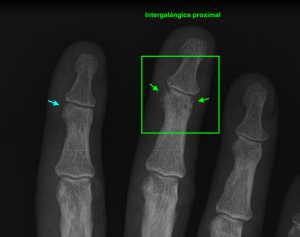

La radiografía revela aumento de las partes y se refrenda en la ecografía como puedes ver en la imagen aunque aún no hay afectación en el hueso en el caso que te presento hoy.

Llegado el caso está enfermedad tiene una clasificación según su afectación tipo 1 a tipo 3 y su diagnóstico es radiográfico.

Ecografícamente y debido a su levedad, en el caso de hoy solo observamos cambios en las partes blandas de la cara lateral de la cabeza del quinto metatarsiano, este tejido se muestra heterogéneo, la cortical del hueso ligeramente prominente sin afectación de la misma.